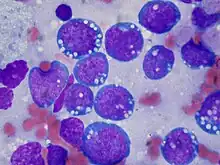

- Lymphoma and myeloma, derived from cells of the immune system.

Lymphoma_MG_stain.jpg.webp) Myeloma

Myeloma Sarcoma